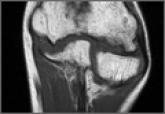

Avascular Necrosis of Trochlea After Supracondylar Humerus Fractures in Children

Avascular necrosis (AVN) is a rare but important complication after supracondylar humerus fractures. Posttraumatic humerus deformity was first...